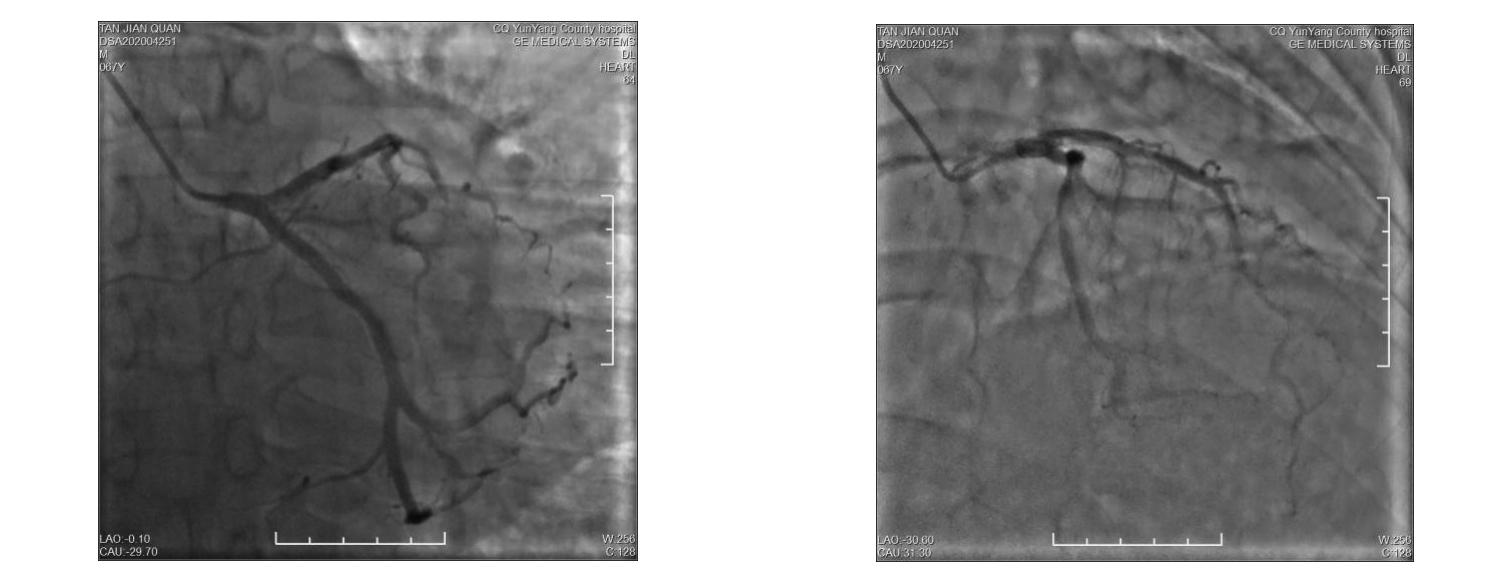

• 疑似雷帕霉素药物洗脱支架术后Kounis综合征1例

2024, 49(1):97-100. DOI: 10.13406/j.cnki.cyxb.003409

摘要 (42) HTML (15) PDF 1.14 M (104) 评论 (0) 收藏

摘要: